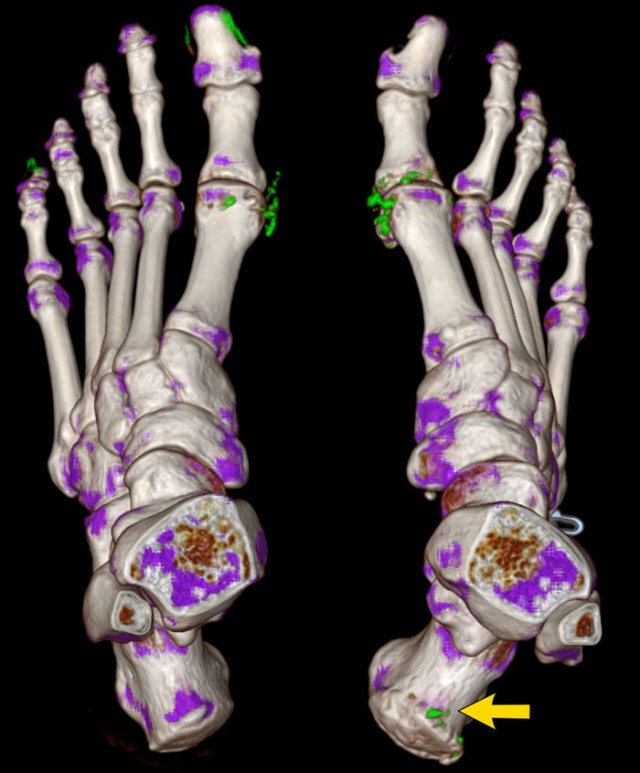

Dual Energy CT in a patient with gout and urate crystal depositions Dual Energy CT in a patient with gout and urate crystal depositions

Dual Energy CT of the same patient with gout showing the urate crystal depositions.

In this 3D reconstruction the crystal depositions are color coded green and can be seen surrounding the MTP joints and at the insertion of the right achilles tendon (arrow).

The green pixels in the nail beds of digitus 1 and 5 on the left are artifacts caused by keratin in thickened nails.

Dual Energy CT is a noninvasive method of urate crystal detection that can make joint aspiration unnecessary.

Dual Energy CT simultaneously scans the subject at two different energy levels.

Because urate crystals show different attenuation at these energy levels, the crystals can easily be identified with high accuracy.

Another case with typical gout tophi and juxtaarticular erosions on plain films.

Dual Energy CT shows gout attenuation in MTP1, MTP2 and interphalangeal joints of the 3rd digit.

DECT is useful for the diagnosis when findings are not so typical.

It is also very useful to show the extent of disease.

In this case, a bone tumor was suspected.

There are definitely some findings that could support the diagnosis of an osteosarcoma of chondrosarcoma.

However, this was proven to be gout.

Continue with the DECT images...

With these DECT images, nobody was in doubt anymore.